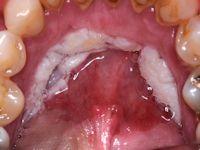

Orale leukoplakie is een witte verkleuring en verandering van het mondslijmvlies. Het komt vaak voor (bij circa 13% van de bevolking kunnen witte verkleuringen worden aangetroffen). Leukoplakie is een beschrijvende diagnose, het histologisch beeld van leukoplakie kan variëren van hyperkeratose met of zonder epitheeldysplasie, via carcinoma in situ en micro-invasief carcinoom tot invasief carcinoom. Klinisch worden er 2 varianten onderscheiden: homogene en niet-homogene leukoplakie. Homogene leukoplakie is een egaal witte verkleuring met een vlak, dun en glad oppervlak. Niet-homogene leukoplakie is een witte of witrode afwijking die irregulair vlak, nodulair of exofytisch kan zijn. Het homogene type is vaak asymptomatisch, terwijl het niet-homogene type gepaard kan gaan met pijn of hinder. Orale leukoplakie kan overgaan in een carcinoom van de mondholte; 17-35% van de carcinomen ontstaan uit preëxistente afwijkingen, vaak leukoplakie. Leukoplakie komt ook voor op andere slijmvliezen (leukoplakie van de penis of de vulva).

Leukoplakie kan worden veroorzaakt door externe factoren zoals roken, mechanische irritatie, candida. In dat geval kan het verdwijnen door die factoren weg te nemen. Indien het na 2-4 weken niet is verdwenen dan gaat het om echte leukoplakie, en is er kans op epitheeldysplasie: het advies is om een biopt af te nemen.

De mate van dysplasie wordt onderverdeeld in gering, matig en ernstig. Er is een direct verband tussen de mate van dysplasie en de kans op maligne ontaarding. De kans op maligne ontaarding binnen 5 jaar is ongeveer 5%. Het ontstaat vooral in niet-homogene leukoplakie.

Risicofactoren voor het ontstaan van leukoplakie zijn roken, alcoholgebruik, Candida infectie, HPV infectie, deficiënte voeding (vooral tekort aan vitamine A, B12, C, beta-caroteen, foliumzuur). Leukoplakie ontstaat meestal vanaf 30 jaar, de meesten zijn ouder dan 50 jaar. De kans op maligne ontaarding is verhoogd bij aanwezigheid van één van de volgende kenmerken: epitheeldysplasie in het biopt; niet-homogene type; vrouwelijk geslacht; langer bestaande leukoplakie; leukoplakie bij niet-rokend persoon; locatie in de mondbodem of op de tong; aanwezigheid van C. albicans.